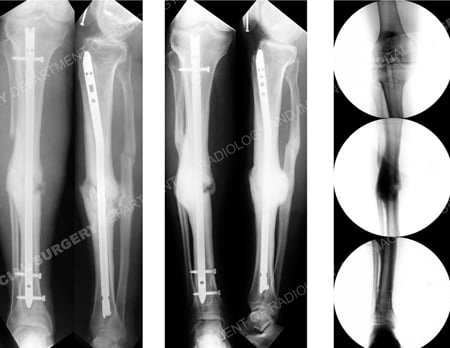

post-operative radiographs following correction of mid-shaft tibial deformity from case example presented by the orthopedic trauma service at hospital for special surgery.

Immediate postoperative radiographs (2 left images) following correction of deformity and insertion of a reamed IM nail and screws including a dynamic proximal dynamic interlocking screw; radiographs 1 year following the index surgery (middle 2 images) illustrate a healed tibia nonunion; fluoroscopic images (right image sequence; top to bottom) following removal of the reamed IM nail (13 months following the index surgery).